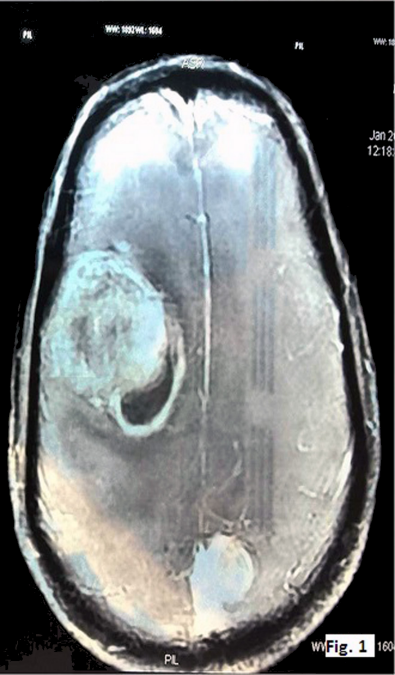

A 50-year-old male presented with headache since the past two months. He also complained of weakness in both upper and lower limbs and altered sensorium for the past fifteen days. On physical examination, the patient was conscious with a GCS of E4M6V4. The power was reduced on the left side (3/5), but maintained on the right side (5/5). Computed tomography (CT) revealed well defined hetero-dense masses measuring 5x4 cm and 2x2 cm in the right and the left parietal region respectively with surrounding edema and mass effect (Figure 1 [Fig. 1]). A diagnosis of glioblastoma multiforme was suggested. Total excision of both the masses was done and they were sent for examination. Histopathology of both lesions showed a tumor with cells arranged diffusely in sheets as well as scattered singly. The cells had abundant amounts of eosinophilic cytoplasm, eccentrically placed nuclei, and prominent nucleoli. Areas of high mitotic activity and necrosis were also noted (Figure 2 [Fig. 2]). The possibilities considered were glioblastoma multiforme, metastases, melanoma, plasmacytoma, and rhabdoid meningioma. On IHC (immunohistochemistry), the tumor cells were negative for GFAP, CK, HMB-45 and showed diffuse positivity for D2-40 and vimentin. Focal positivity for EMA was also observed. The high mitotic activity was highlighted by Ki67 positivity demonstrating a mean labeling index of 15% (Figure 3 [Fig. 3]). Absence of pigment and HMB-45 reactivity ruled out a melanocytic lesion. Absence of mott cells and CD 138 reactivity ruled out plasmacytoma. Absence of any other primary lesion on imaging and CK negativity eliminated metastatic carcinoma. GFAP negativity excluded the possibility of glioma. Finally, EMA, D2-40, and vimentin positivity confirmed the meningeal nature of the tumor cells. Thus, a final diagnosis of bilateral rhabdoid meningioma was rendered. Often, the presence of classical areas of meningothelial appearance in the tumor help in reaching the diagnosis [1]. However, these were absent in the present case. Postoperatively, there was improvement in the neurological deficit and subsequently, the patient was put on radiotherapy. He received 30 cycles of radiotherapy with a radiation dose of 60 Gy. Till one year follow-up, the patient is asymptomatic and doing well.

Figure 1: CT image showing hetero-dense lesions in both right and left parietal areas